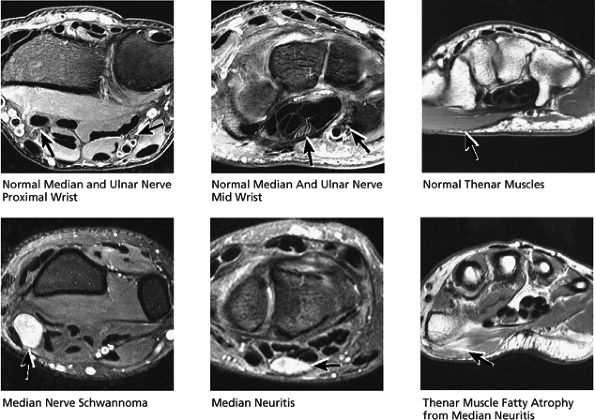

FIGURE 10.31 ● Normal coronal anatomy. (A) Fatty atrophy or denervation of the thenar muscles raises the possibility of median neuritis, and in such cases the median nerve is closely examined for enlargement or increased signal. (B) Tenosynovitis of the flexor tendons with fluid in the tendon sheaths can occasionally cause enough mass effect on the median nerve to cause median neuritis. (C) The first carpometacarpal joint (the articulation between the trapezium and the base of the first metacarpal) is a common location for degenerative arthrosis, often visualized at the corner of a coronal image. (D) Fluid in the pisotriquetral recess is a common finding. In the absence of other findings such as degenerative changes at the joint, a small amount of fluid in the pisotriquetral recess is probably of no significance. (E) Fractures of the distal scaphoid extending to the articular surface should be characterized as entering the lunate fossa (the radial articulation with the lunate) or the scaphoid fossa (the radial articulation with the scaphoid). Such articular extension, particularly if depressed or displaced, can lead to significant radiocarpal degenerative disease. (F) The triscaphe joint consists of the distal pole of the scaphoid articulating with the trapezoid and trapezium and is considered the second most common site of wrist arthrosis. (G) The proximal row should normally form a continuous smooth convex curve. Any subtle offset of the triquetrum from the lunate, or the scaphoid from the lunate, is suggestive of a tear of the lunotriquetral or scapholunate ligaments. (H) The triangular fibrocartilage attachment to the radius may attach to hyaline articular cartilage, and it is important not to mistake the gray cartilage signal at the attachment for a tear, which is usually of fluid signal intensity. (I) The proximal pole of the hamate may occasionally articulate with a normal variant type II lunate facet located on the distal ulnar aspect of the lunate. When this occurs, degenerative changes are visualized at the hamate-lunate articulation in almost half of cases. (J) Small degenerative perforations in the membranous component of the scapholunate ligament are not uncommon in older patients, and in this population they may be asymptomatic and unassociated with carpal instability. (K) The TFC has insertions at the tip and at the base of the ulnar styloid. Therefore, fractures at the base of the ulnar styloid may disrupt the integrity of the TFC and potentially cause distal radial ulnar joint instability. (L) On coronal images through the dorsal wrist, the dorsal component of the scapholunate ligament may occasionally be discretely identified. The dorsal component is considered the most important of the scapholunate ligament components for maintaining carpal stability. (M) Another significant and commonly overlooked location for degenerative arthrosis is at the base of the third metacarpal, where a common protuberance, called a carpal boss, articulates with the capitate. Unusually prominent carpal bosses may become hypertrophic and articulate with a spur on the distal capitate, which can often be palpated by the patient as a tender bump just beneath the skin along the dorsal wrist. (N) Ganglion cysts can be visualized extending through the dorsal capsular ligaments on coronal images through the dorsal wrist. Common sites of origin are the scapholunate ligament, the triscaphe joint, and the third carpometacarpal joint (often associated with degenerative change at a carpal boss).

FIGURE 10.32 ● Normal axial anatomy. (A) Fractures of the hook of the hamate, commonly occult on plain films, are easily visualized on axial MR images through the hamate. (B) The flexor carpi radialis is visualized cradled by the hook of the trapezium. This is a common location for tenosynovitis and tendinosis of the flexor carpi radialis tendon. (C) The thenar muscles (abductor and flexor pollicis brevis) are visualized volar to the radial aspect of the distal carpus. Median neuritis should be suspected when selective fatty atrophy or denervation of the thenar muscles is visualized. (D) The median nerve within the carpal tunnel may display evidence of median neuritis, such as increased signal or enlargement. A mass lesion of the carpal tunnel at this level may cause mass effect within the carpal tunnel and impinge the median nerve. (E) The pisotriquetral joint is a common location for severe degenerative arthritis and synovitis, associated with significant ulnar-sided pain. (F) The extensor pollicis longus crosses obliquely dorsal to the extensor pollicis longus and brevis tendons. This is a not uncommon location for tears of the extensor pollicis longus tendon. (G) The scapholunate articulation is a common location for ganglion cysts, usually found directly dorsal to the scapholunate ligament. Even small dorsal ganglion cysts in this location can be exquisitely tender and painful. Often, a small neck of fluid signal extends from the dorsal ganglion cyst back toward the scapholunate ligament, and in certain cases a small perforation of the scapholunate ligament can be suggested. (H) The extensor pollicis brevis and abductor pollicis longus tendons are located lateral to the distal radius. Tendinosis and tenosynovitis of these tendons is known as de Quervain's stenosing tenosynovitis. (I) Not uncommonly the extensor carpi ulnaris tendon is subluxed over the ulnar styloid, particularly when the patient is supinated, with the ulnar styloid pointing dorsally. This is not necessarily an abnormal finding, particularly when the extensor carpi ulnaris tendon otherwise appears normal. (J) The triangular shape of the TFC complex is best appreciated on axial images, with the apex of the triangle attaching at the ulnar styloid and the broader base of the triangle attaching at the radius. (K) The distal radioulnar joint is examined in the axial plane to view the alignment of the radius with respect to the ulna. The ulna lies within the concave groove in the medial aspect of the radius called the sigmoid notch, and the two bones lie grossly in the same plane. Mild apparent dorsal shift of the ulna with respect to the radius is normal when the wrist is scanned in full pronation (the ulnar styloid pointing ulnar-volar). (L) When the triangular fibrocartilage is torn, or if there is a displaced fracture at the base of the ulnar styloid, the distal radial ulnar joint may become somewhat destabilized, ultimately resulting in degenerative arthrosis and synovitis. Another cause of distal radioulnar joint degenerative change is the ulnar impingement syndrome, in which a short ulna erodes the ulnar aspect of the distal radius.